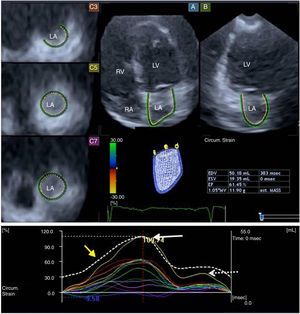

Three-dimensional speckle-tracking echocardiographyDuring the same echocardiographic examination, 3D datasets were acquired in apical view using a commercially available 1-4MHz PST-25SX matrix-array transducer (Toshiba Medical Systems, Tokyo, Japan).3 During end-expiratory breath-hold and six ECG-gated beats, six wedge-shaped subvolumes were acquired to create the LV full volume. Off-line analysis of the 3D datasets was performed using 3D Wall Motion Tracking software, version 2.5 (Toshiba Medical Systems, Tokyo, Japan). Apical 2-chamber (AP2CH), 4-chamber (AP4CH), and short-axis views at different levels of the left atrium (basal, mid, and superior) were automatically selected at end-diastole (Figure 1). Non-foreshortened AP2CH and AP4CH views were determined by finding the largest long-axis LA dimensions, then the mitral annulus and the LA apex were marked manually. The LA appendage and pulmonary veins were excluded from the examination. Following LA border detection at the end-diastolic reference frame, wall motion tracking was performed automatically in 3D space throughout the cardiac cycle. The shape of the LA was corrected if needed. Due to the absence of an LA-specific segmentation model, the left atrium was automatically divided into 16 segments using standard LV segmentation.9

Apical 4-chamber (A) and 2-chamber views (B), and different parasternal short-axis views at basal (C3), mid (C5) and superior (C7) left atrial regions, extracted from the three-dimensional volume. A three-dimensional wireframe reconstruction of the left atrium based on three-dimensional speckle-tracking echocardiographic analysis together with volumetric data and segmental (circumferential) time-strain curves are also presented. White, dashed and yellow arrows represent segmental (systolic) peak strain, (late-diastolic) strain at atrial contraction and global time-volume curve, respectively. LA: left atrium; LV: left ventricle; RA: right atrium; RV: right ventricle.

Using the ECG-gated 3D-LA model, end-systolic maximum volume (Vmax), diastolic volume before atrial contraction (VpreA) and end-diastolic minimum volume (Vmin) were measured in each case10–16 (Figure 1). From the three volumes, the following features of different phases of LA function were also calculated:

The following parameters of LA deformation were assessed13–18: global, mean segmental and regional (basal, mid and superior) radial (RS), longitudinal (LS), circumferential (CS), area (AS) and 3D (3DS) strain. Using LA time-strain curves, the first peak (feature of systolic LA reservoir function) and the second peak (strain at atrial contraction, a characteristic of LA booster pump function) were calculated in each patient.